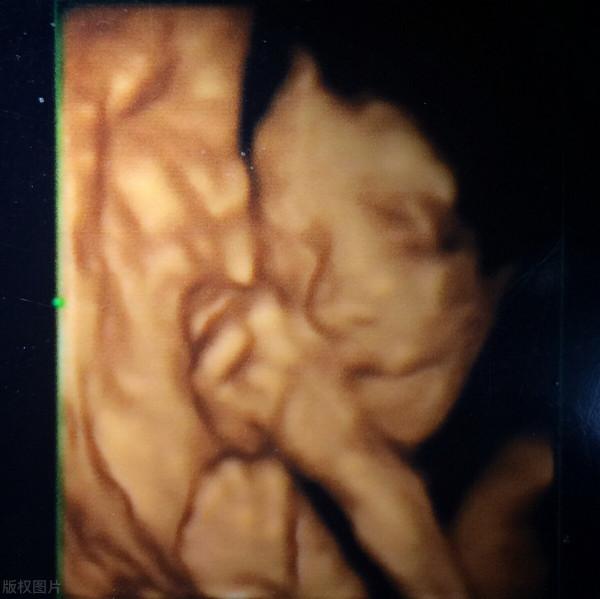

四維大排畸一般在孕23周至26周做,主要是看孩子的脊柱、大外觀等等有沒有明顯的缺陷。

四維的圖片會給出孩子臉部的特寫,大致都可以看出孩子長得像爸爸還是媽媽了。

可以說,這是我們和孩子的第一次“正式見面”。

如果在此之前我們對孩子還是“一無所知”的話,那麼做四維就是讓我們和孩子第一次建立起了比較明確的連結。

我家大寶做四維時睜開了眼睛,很多朋友說這不可能,在羊水裡怎麼可能睜開眼睛,可報告圖片上確實是睜著眼睛的。

由此我對老公說,這孩子將來可能會比較敏感和早熟,很可能是超聲波的噪音打擾了他,所以他睜了一下眼睛,正好這一瞬間被儲存了下來。

果不其然,大寶確實是個對外界的評價很敏感的孩子,並且比同齡的男孩子顯得早熟。

所以說,寶爸們要珍惜這第一次和孩子“見面”的機會,說不定會一下子喚起內心父愛的火苗。

有些私立醫院做四維的時候寶爸可以陪同檢查,檢查的地方還會有一個放大的顯示屏,可以讓寶爸寶媽更能看清孩子的樣子,還可以看到孩子在肚子裡的各種動作。有些醫院還會把四維彩超做成光碟,留給爸爸媽媽做紀念。